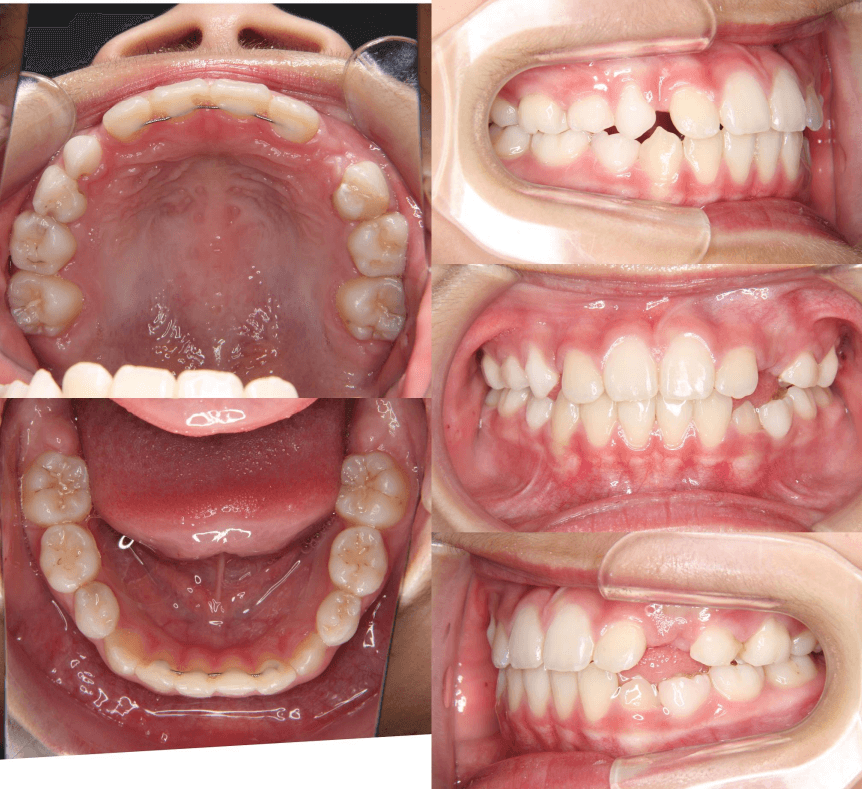

| 年齢・性別 | 8歳9ヶ月の女児 |

|---|---|

| 主訴 | 歯並びの乱れを気にされて来院された患者様です。将来的なスペース不足と歯のねじれ(翼状捻転)が懸念されました。 |

| 治療期間・回数 | 2年10ヶ月・19回 |

| 費用 | 430,000円(税別) |